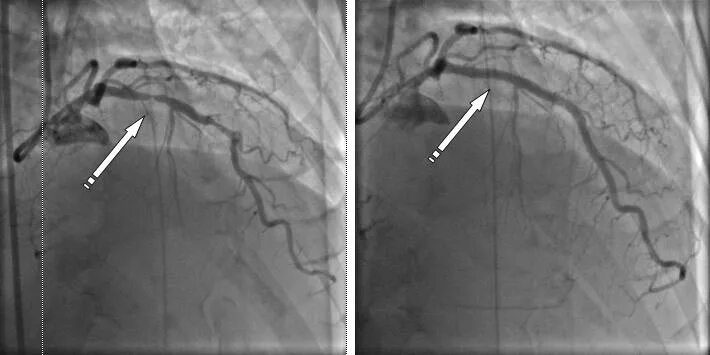

Стеноз проксимального отдела